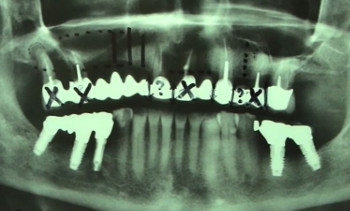

Publié le 15/02/2017Un patient présente de nombreux abcès au maxillaire sous un bridge complet céramo-métallique réalisé depuis moins de 2 ans.

L’utilisation du rayonnement laser diode sous H²O² va permettre de décontaminer les sites osseux receveurs.

L’intervention est réalisée sous anesthésie générale. Elle comportera : extractions, curetages, décontaminations, comblements osseux sinusiens, crestal, alvéolaires et péri-apical et pose des implants.